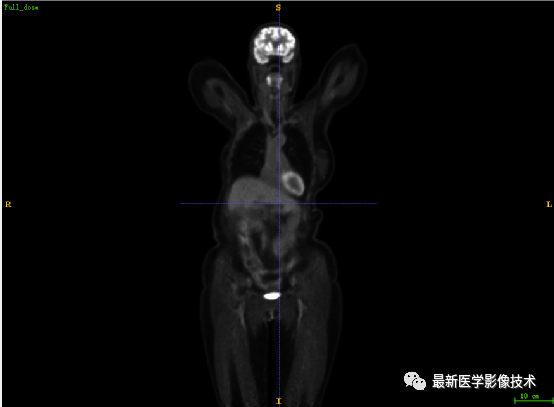

7.2、低剂量4重建结果

第一张是低剂量4的PET图像,第二张是full剂量PET图像,第三张是网络重建的PET图像。